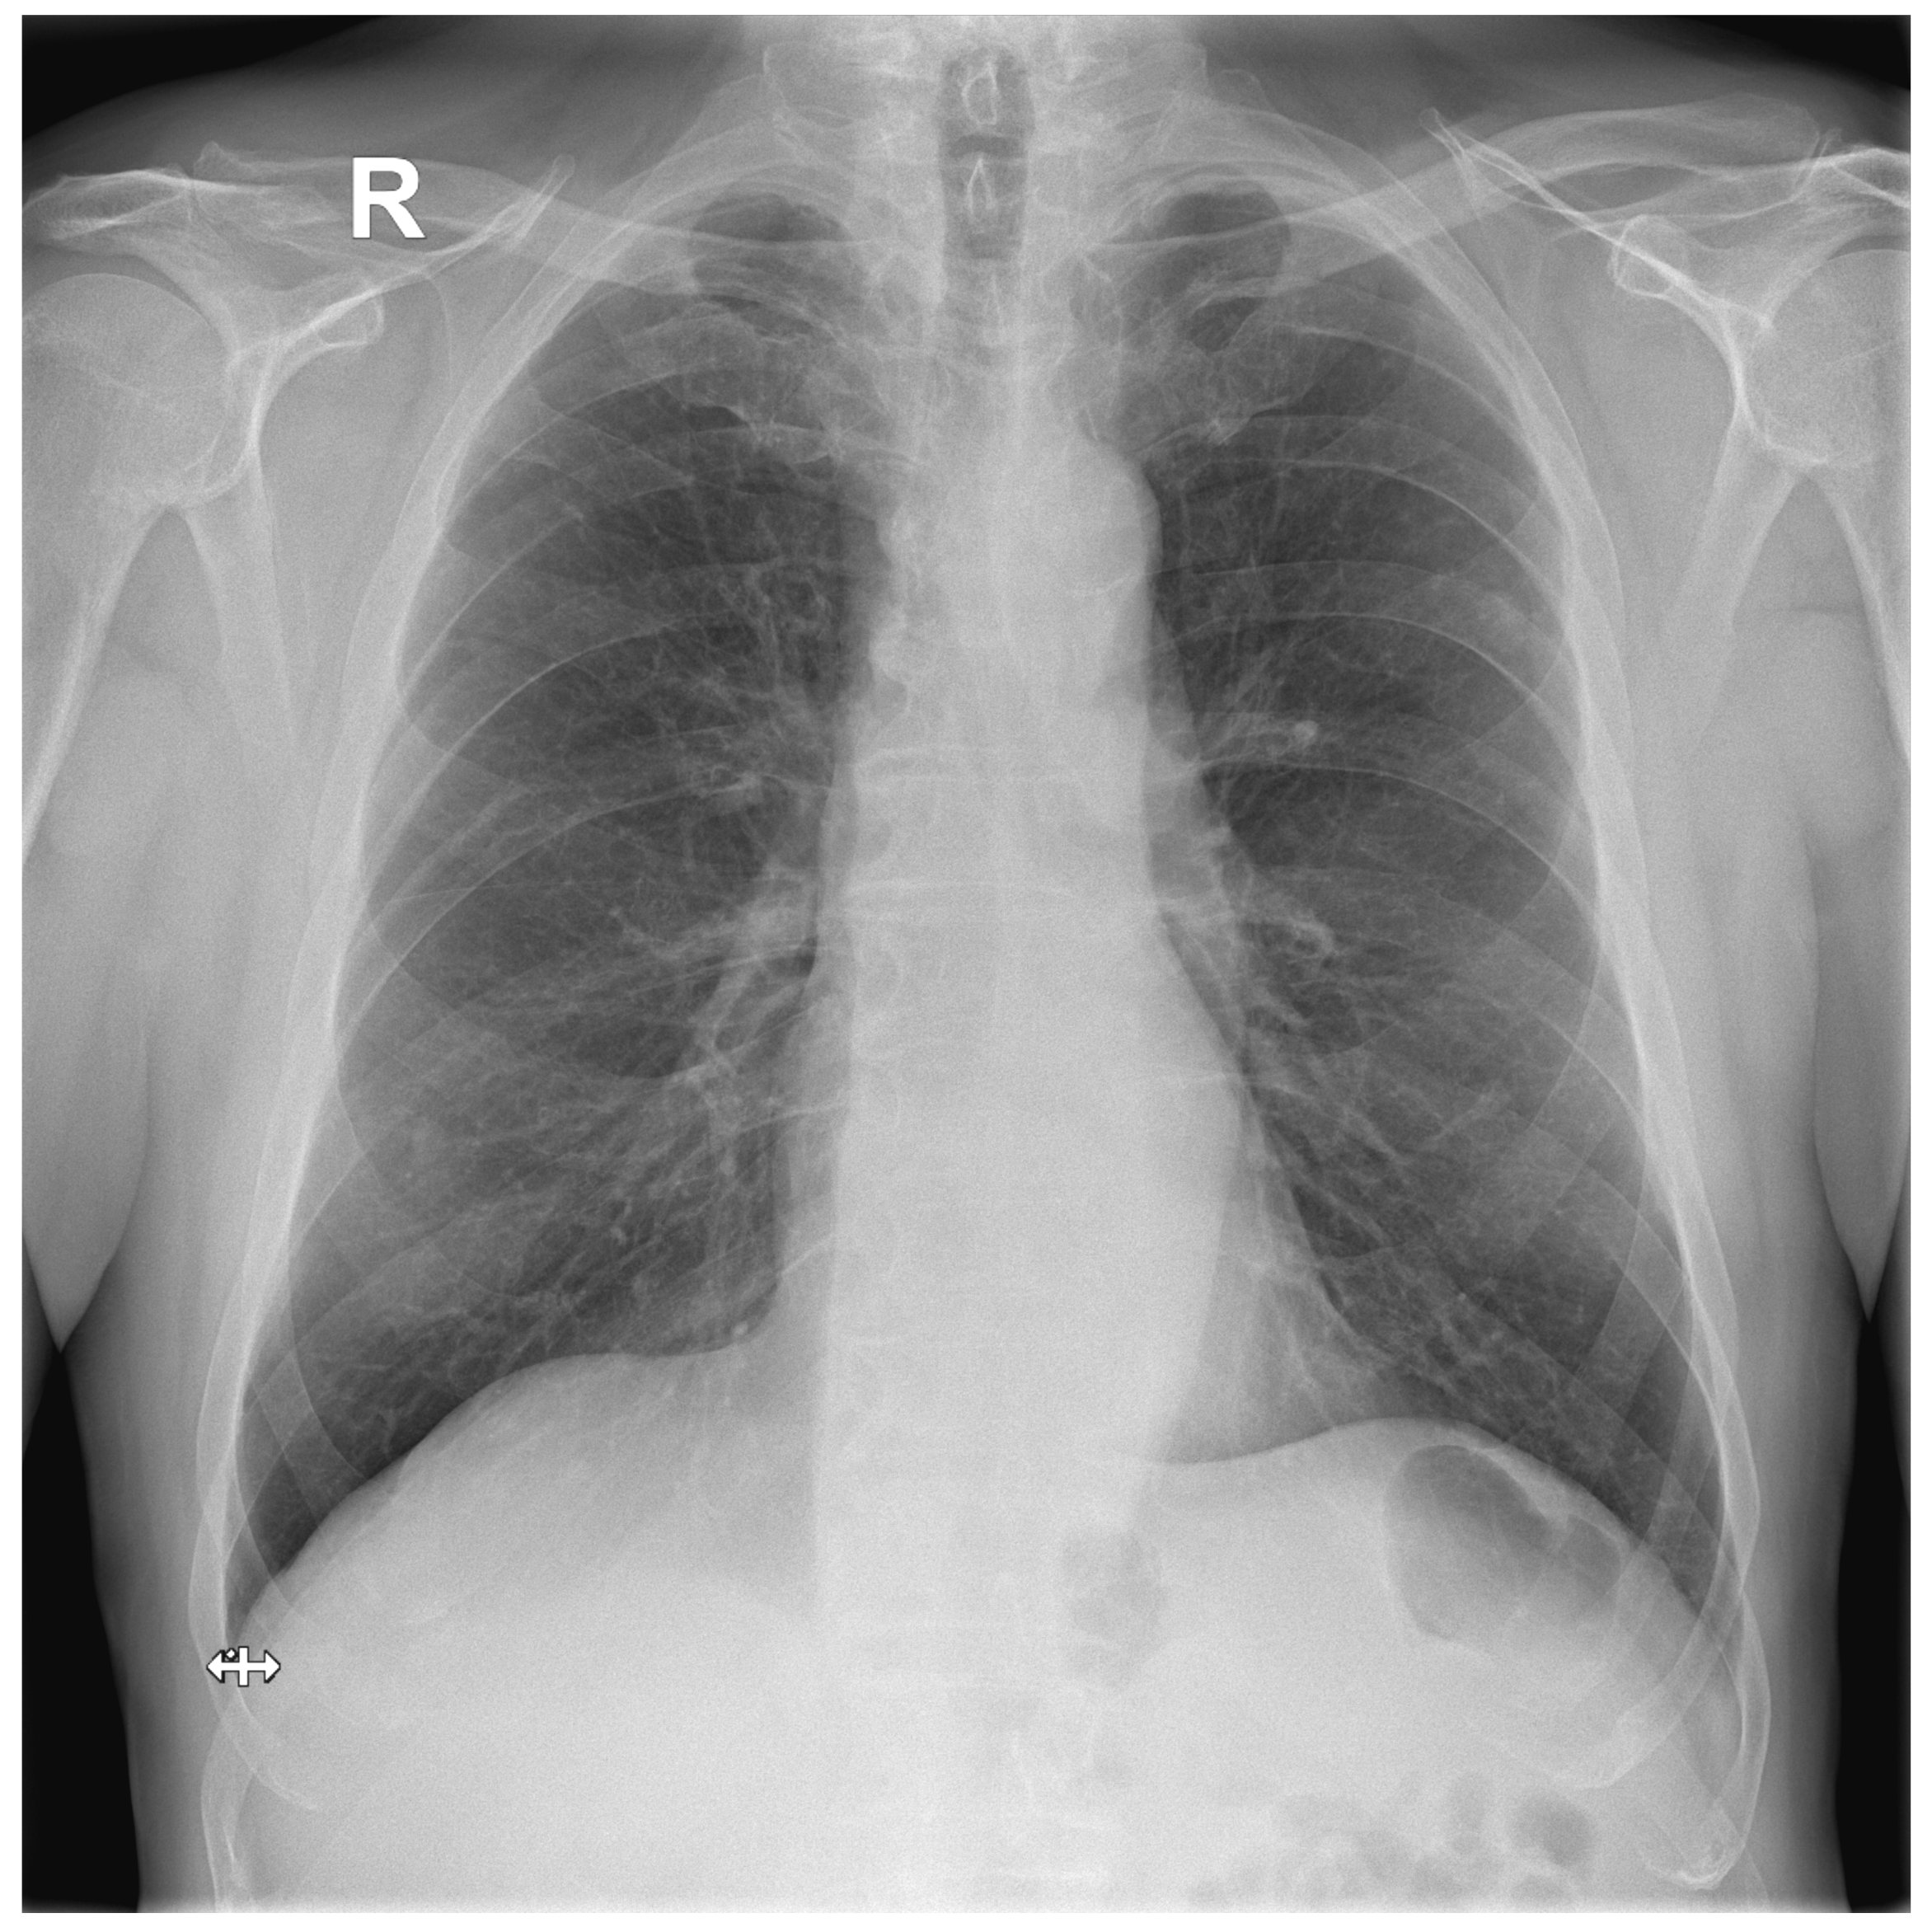

A total of 127 images with established ground truth were evaluated: 40 (31.5%) with a finding and 87 (68.5%) without any finding. The DLAD correctly identified 37 images as abnormal and 56 images as normal (73.2% in total). A total of 31 (24.4%) normal images were incorrectly classified as abnormal. The higher false positive rate was expected since DLAD was trained to assign even suspect findings as abnormal. Another three (2.4%, Figure A2, Figure A3, Figure A4) images were incorrectly classified as without any finding, even though they were with findings (false negative rate) (Table 3).

Figure A4.

False Negative image #3 incorrectly classified by DLAD software during the retrospective study. The software failed to detect a rib fracture. Assessed radiologists #5f0 and #630 also incorrectly classified this image as Normal. Assessed radiologist #442 classified the image correctly as Abnormal but failed to locate a rib fracture.